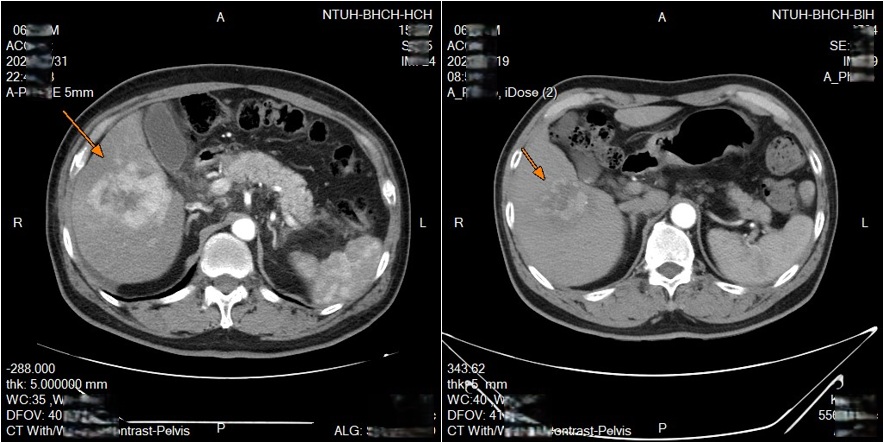

新竹一名63歲男性,先是得了淋巴癌,而後在治療期間又發現肝腫瘤,確診肝癌,醫療團隊安排進行鎖骨下導管置放於肝動脈灌注化療(HAIC),歷經兩次療程,腫瘤明顯縮小。台大新竹分院影像醫學部醫師游加樂表示,HAIC技術近年在台灣逐漸興起,已成無法接受根治性手術或栓塞術的中晚期肝癌病人重要治療選項之一。

透過可移動式的導管放置,每次治療後都可以重新調整導管的位置,若導管移位或堵塞,可以迅速處理,減少併發症的發生。臨床上,不少病人對治療產生良好反應,部分病人在影像追蹤中可見腫瘤縮小或消失,顯示治療具相當潛力。